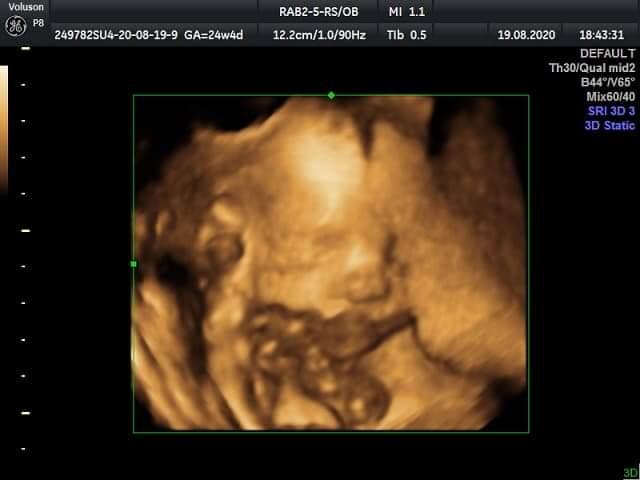

I-a murit fiica după ce medicii nu au primit-o la maternitate să nască: "Au venit mămici cu cordonul ieşit, doar nu o să moară la tine"